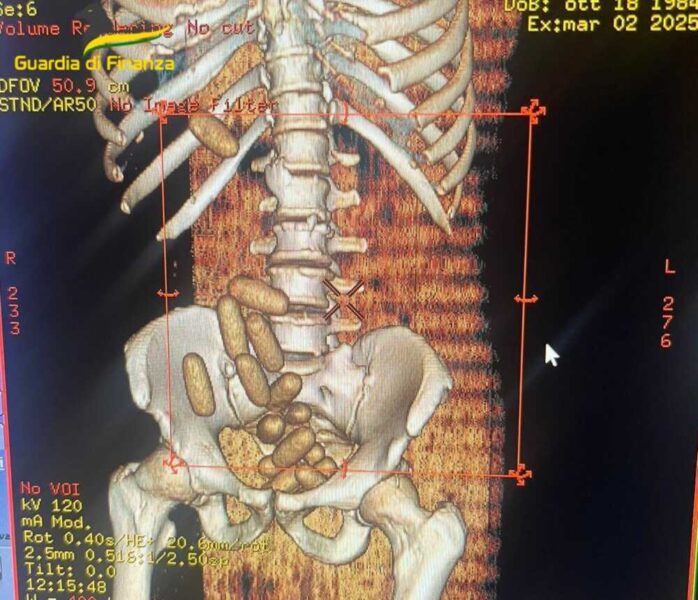

La conferma dei dubbi dei finanzieri è arrivata grazie al fiuto del cane antidroga “Jachpot”. I militari hanno quindi deciso di approfondire l’ispezione, con accertamenti medici presso l’Ospedale “San Paolo” di Civitavecchia, che hanno fatto rilevare la presenza di ben 18 ovuli occultati nella cavità addominale del soggetto fermato.